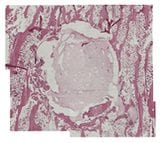

genex Implantation

6 Weeks

(Large animal model. Decalcified histology H&E stain)

genex restores bone to normal trabecular structure in 36 weeks1